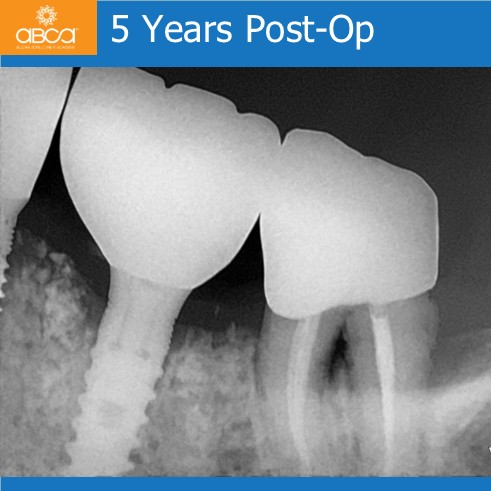

Stable bone height around the implant 5 years after augmentation, even though the patient is an 82-year-old smoker with bad oral hygiene. Stability in the area also supports the surrounding, compromised teeth.